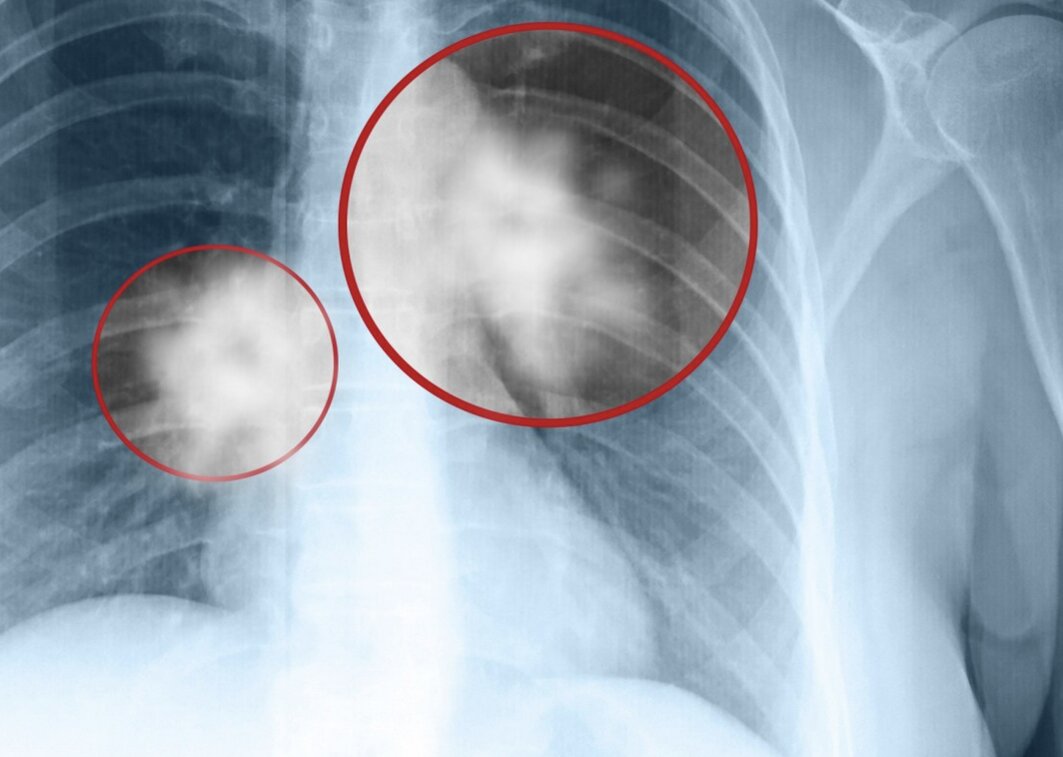

Old  Default Vợ chồng lần lượt mắc ung thư phổi khiến bác sĩ bàng hoàng: "Rốt cuộc chuyện gì đã xảy ra trong nhà này?"

Mới đây, trang Sohu đưa tin, một câu chuyện gây chấn động y giới tại Trung Quốc: Một cặp vợ chồng lần lượt mắc ung thư phổi, khiến bác sĩ không khỏi đặt câu hỏi: "Gia đình này rốt cuộc đã trải qua điều gì?".

Theo thông tin từ bệnh viện, người vợ, một phụ nữ khoảng 60 tuổi, phát hiện khối u phổi kích thước 3cm khi đi chụp X-quang trong một lần khám sức khỏe tổng quát. Bà cho biết đã vô cùng bàng hoàng. Chồng bà đã qua đời vài năm trước vì ung thư phổi giai đoạn cuối, khi được phát hiện thì dịch phổi đã đầy, chỉ còn sống được một thời gian rất ngắn.

Nguyên nhân gây ung thư phổi của 2 vợ chồng: Người chồng nghiện thuốc lá nặng, thường xuyên hút trong nhà

Sau khi tìm hiểu, bác sĩ phát hiện nguyên nhân chính gây nên bi kịch này là do người chồng trước đó là người hút thuốc lá rất nặng, thường xuyên hút ngay trong nhà. Điều này khiến cả gia đình tiếp xúc với khói thuốc thụ động, dẫn đến nguy cơ mắc ung thư phổi rất cao.